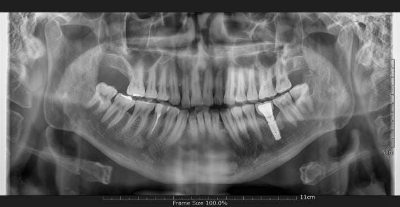

환자분(김ㅇ진님)은 #34 부위에 임플란트 수술을 받으셨습니다. 수술은 약 30분 만에 순조롭게 마쳤습니다.

새벽 2시까지도 감각 이상이 지속되어, 다음날 아침 첫 진료 시간에 내원하시도록 안내했습니다. 검사 후 픽스처를 2mm 짧은 것으로 교체하는 재수술을 진행했고, 다행히 5시간 만에 입술 감각이 회복되었습니다.